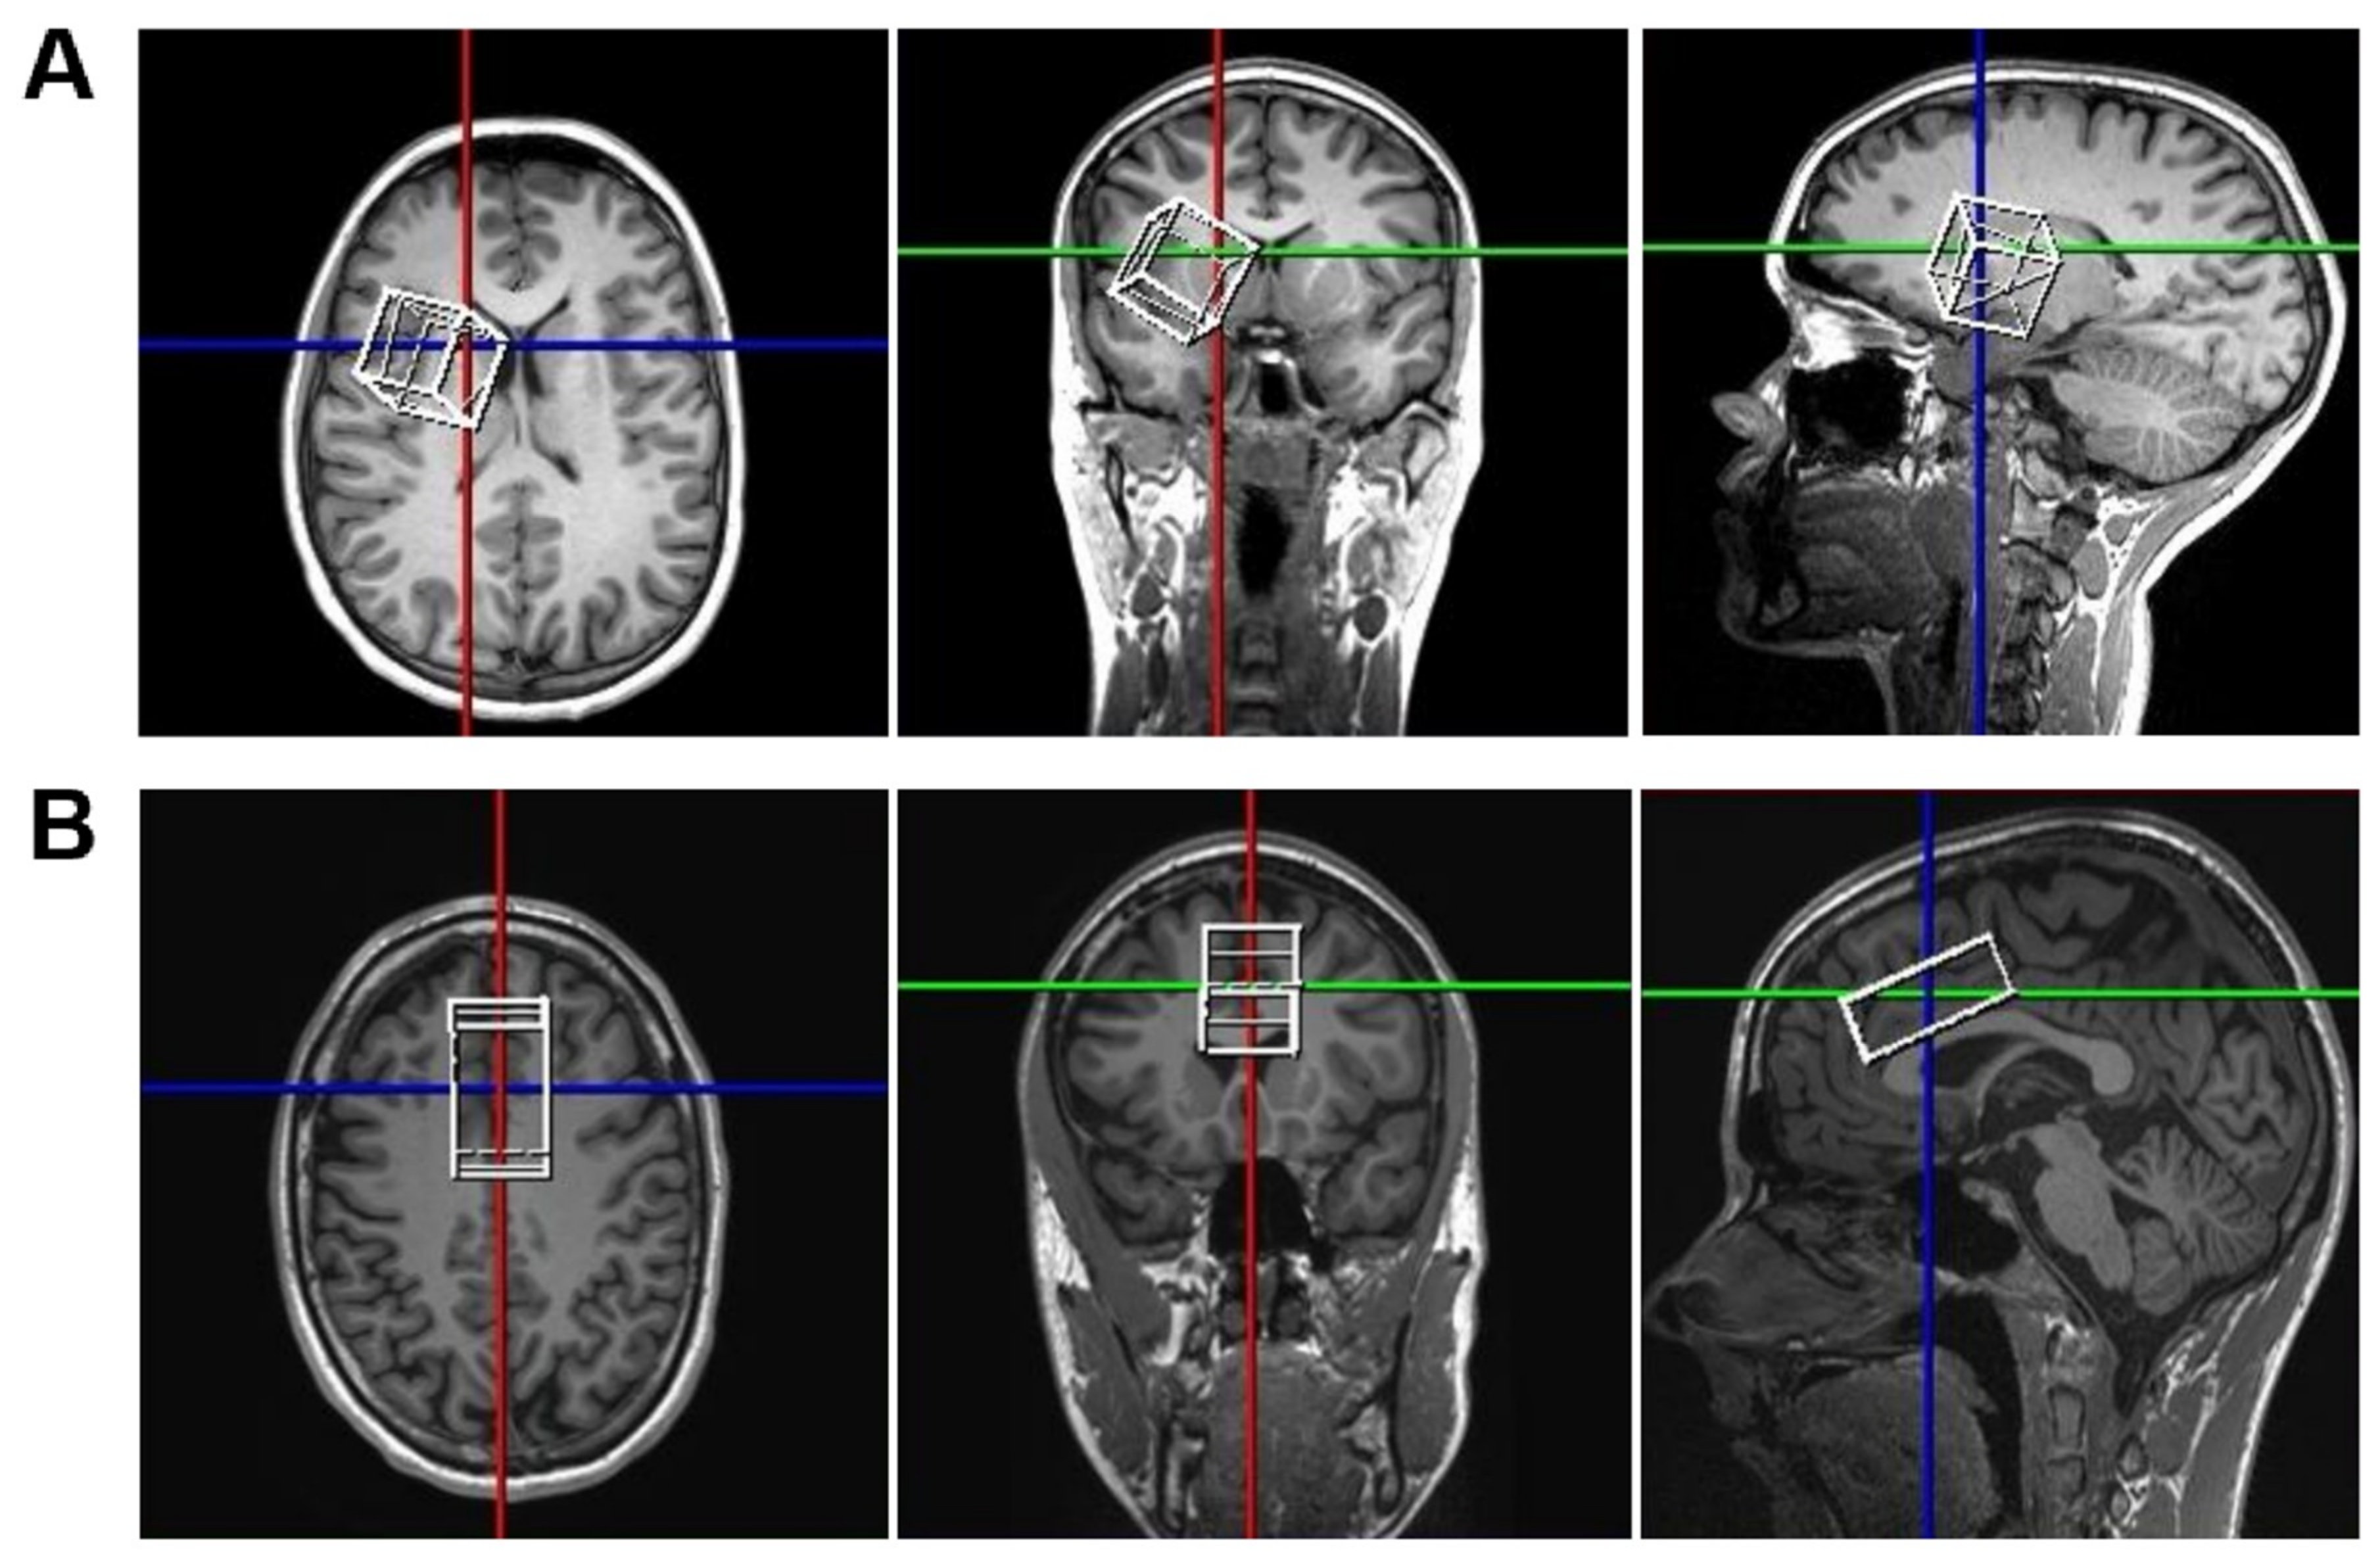

2.4. MRS Data Acquisition and Processing